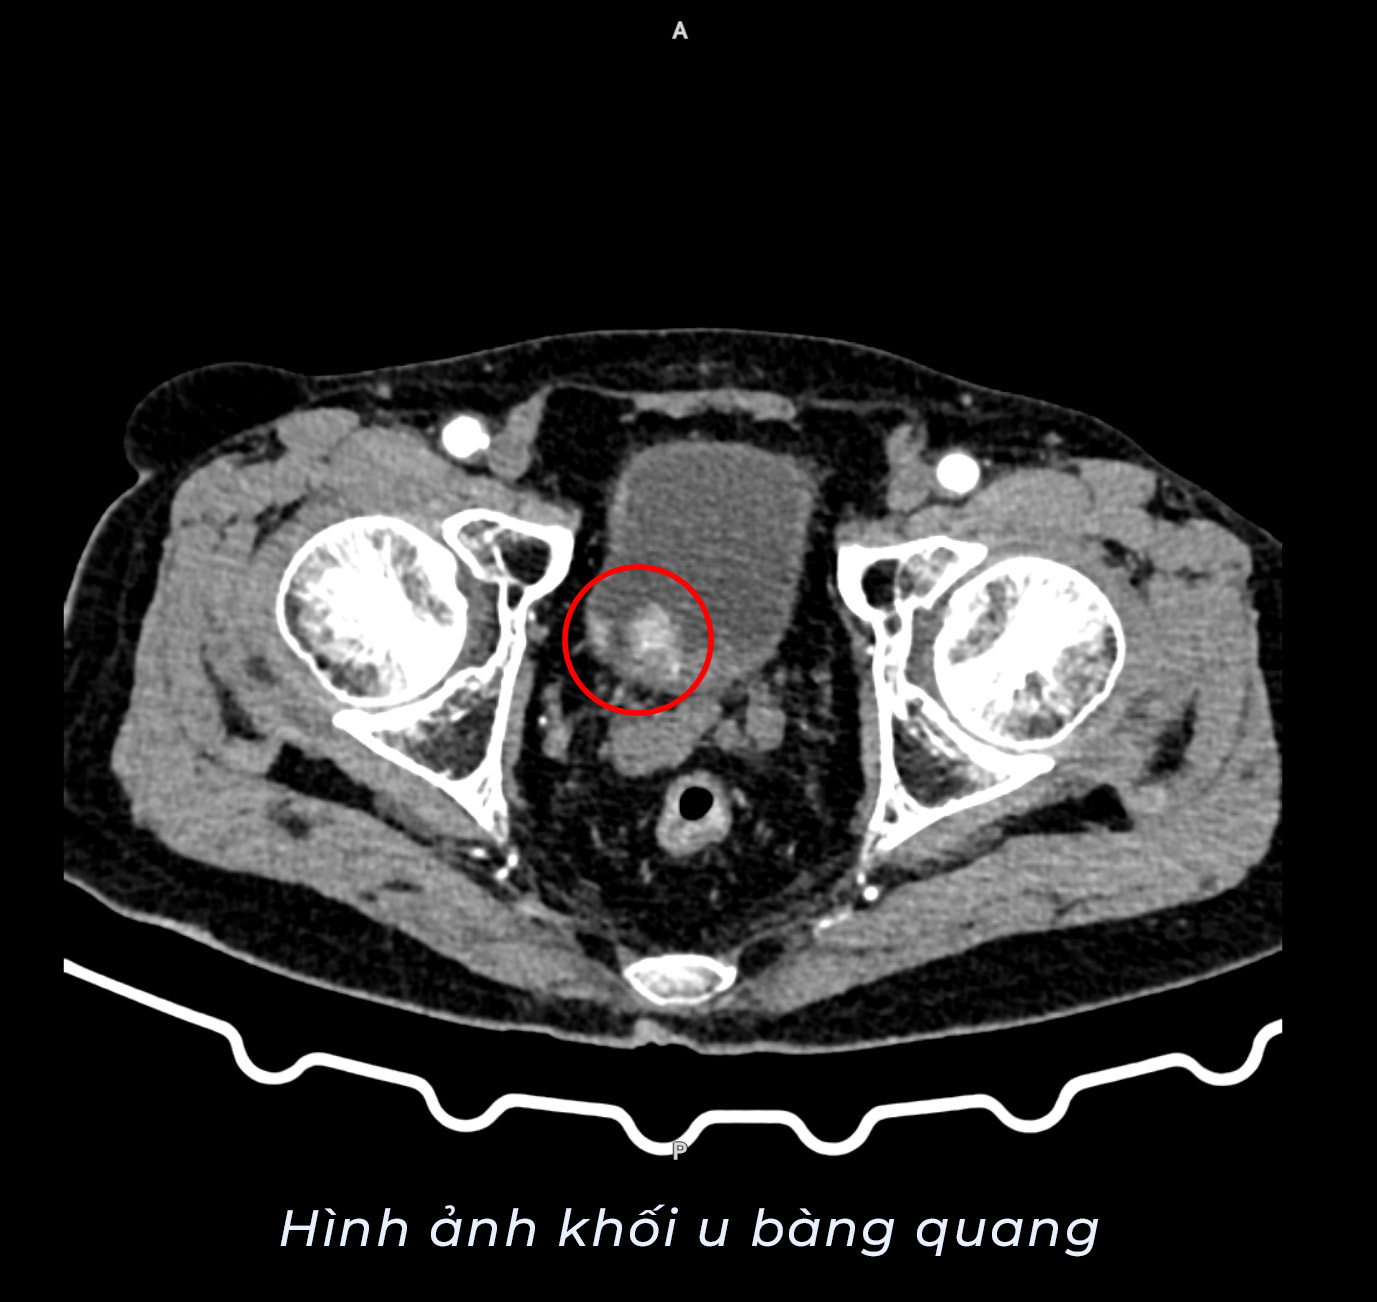

Bệnh nhân P.V.T (87 tuổi, Vân Đồn) nhập viện trong tình trạng tiểu ra máu kéo dài 3 ngày, kèm theo tiểu buốt, tiểu rắt và đau âm ỉ vùng hạ vị. Qua thăm khám và thực hiện các cận lâm sàng cần thiết, hình ảnh siêu âm phát hiện khối giảm âm tại thành bàng quang kích thước 28x18mm. Kết quả chụp cắt lớp vi tính cho thấy thành bàng quang dày không đều, có nhiều nốt giảm tỉ trọng – dấu hiệu nghi ngờ tổn thương u. Sau hội chẩn chuyên môn, bệnh nhân được chẩn đoán u bàng quang trên nền bệnh tăng huyết áp.

Trước nguy cơ khối u tiến triển và ảnh hưởng đến sức khỏe, các bác sĩ đã chỉ định phẫu thuật nội soi cắt u bàng quang. Ca phẫu thuật do TTƯT.BSCKII Nguyễn Huy Tiến – Giám đốc Bệnh viện cùng ê-kíp các bác sĩ, kíp gây mê thực hiện. Với sự phối hợp chặt chẽ và kinh nghiệm chuyên môn, kíp mổ đã tiến hành bóc tách khối u bằng phương pháp nội soi, đảm bảo loại bỏ tổn thương, hạn chế xâm lấn và giảm thiểu tối đa nguy cơ biến chứng.